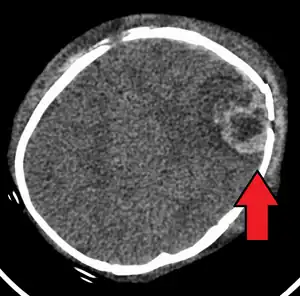

An intraparenchymal bleed with overlying skull fracture from shaken baby syndrome